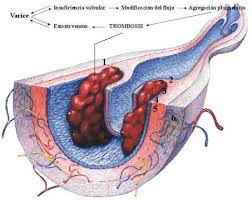

329 × 361 - gimolimpo.com

{"cb":3,"cl":9,"cr":9,"ct":3,"id":"xpk45dB8E7I8sM:","isu":"gimolimpo.com","itg":0,"ity":"jpg","oh":361,"ou":"http://www.gimolimpo.com/Paginas/feblectomia_archivos/image007.jpg","ow":329,"pt":"FEBLECTOMIA","rid":"ZemkA-aU5uHAnM","rmt":0,"rt":0,"ru":"http://www.gimolimpo.com/Paginas/feblectomia.htm","s":"óptima

relación

costo/beneficio","sc":1,"st":"Olimpo","th":235,"tu":"https://encrypted-tbn0.gstatic.com/images?q\u003dtbn:ANd9GcTGBYVUqIaQnxn14lGu1tBPjfbHVvdDHcHstHMXtyqikZScWr_ocw","tw":214}

379 × 281 - gimolimpo.com

{"id":"yi_QeHfQlQD5hM:","isu":"gimolimpo.com","itg":0,"ity":"jpg","oh":281,"ou":"http://www.gimolimpo.com/Paginas/feblectomia_archivos/image003.jpg","ow":379,"pt":"FEBLECTOMIA","rid":"ZemkA-aU5uHAnM","rmt":0,"rt":0,"ru":"http://www.gimolimpo.com/Paginas/feblectomia.htm","s":"Tipos

de

tratamiento","sc":1,"st":"Olimpo","th":193,"tu":"https://encrypted-tbn0.gstatic.com/images?q\u003dtbn:ANd9GcTl_DJI550zaYSZMH-miDVhWY4UK03LOi9ze-1B_FsuneyxG_grOQ","tw":261}

231 × 397 - gimolimpo.com

{"cl":3,"id":"Ofxp5Rburirp3M:","isu":"gimolimpo.com","itg":0,"ity":"jpg","oh":397,"ou":"http://www.gimolimpo.com/Paginas/feblectomia_archivos/image005.jpg","ow":231,"pt":"FEBLECTOMIA","rid":"ZemkA-aU5uHAnM","rmt":0,"rt":0,"ru":"http://www.gimolimpo.com/Paginas/feblectomia.htm","s":"Flebectomía

ambulatoria, es la safenectomía, modificada por el Dr. Oesch, suizo,

que consiste en efectuar la exéresis de la vena, sin lesionar los

tejidos

...","sc":1,"st":"Olimpo","th":294,"tu":"https://encrypted-tbn0.gstatic.com/images?q\u003dtbn:ANd9GcQTaZ5oRKfEvwuBOC5RWCE4GIQU2e4MrfYhpJMx2vBMlbt5qVXNew","tw":171}